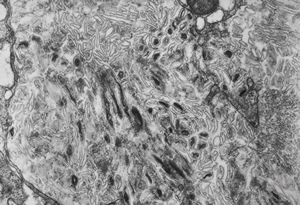

M,54y. | Whipple disease

Whipple disease